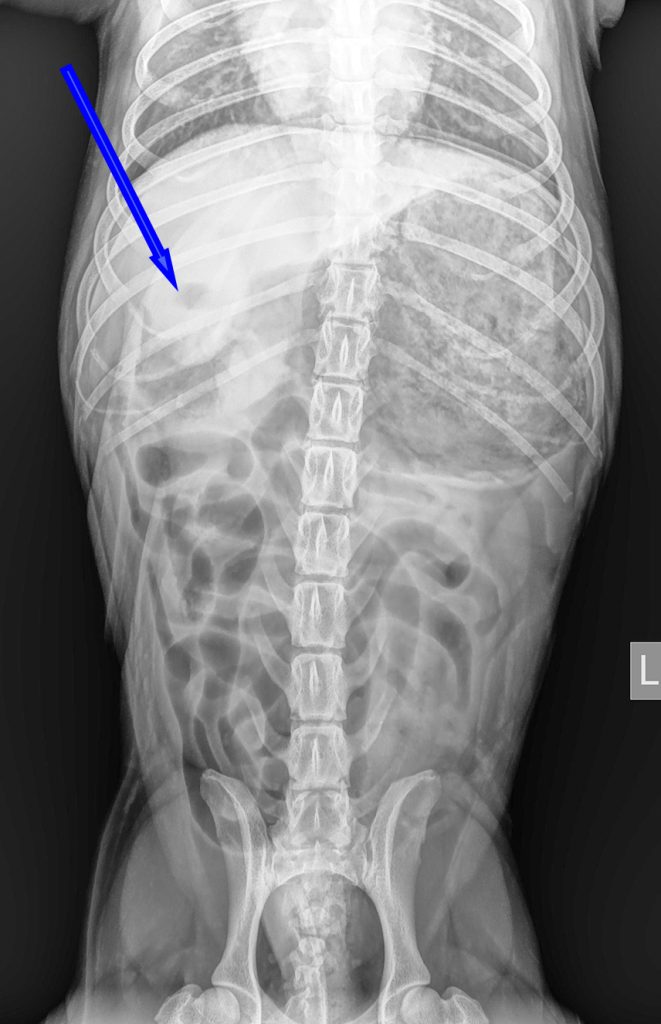

Bij het algemeen onderzoek was de buik gevoelig bij het navoelen en er leek veel gasvorming aanwezig te zijn. Op de röntgenfoto was er een grote maag met veel vulling zichtbaar, waarbij er ook een soort buisvormige structuur aanwezig leek te zijn. Het leek er dus op dat er een vreemd voorwerp in de maag zat. Aangezien Joep al meerdere keren had gebraakt zonder dat er iets uit kwam, was het advies om dit voorwerp operatief te verwijderen.